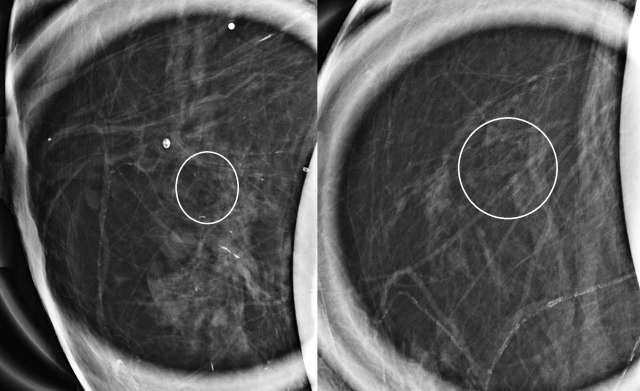

Case: Atypical Ductal Hyperplasia Figure 1

Case 1: Magnification CC implant displaced view (left) and magnification ML implant displaced view (right) from a diagnostic mammogram demonstrate amorphous calcifications with grouped distribution at 12 o’clock at posterior depth located 4 centimeters from the nipple. Pathology demonstrated atypical ductal hyperplasia.